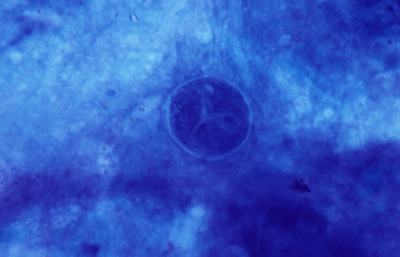

Blanco de Calcofluor

El uso del fluorocromo Blanco de Calcofluor no es excluyente de otras coloraciones, pues al ser en base acuosa no es permanente y la preparación puede lavarse en agua corriente para luego ser coloreadas con Giemsa, PAS u otras coloraciones, con el fin de reconfirmar los hallazgos microscópicos y volverlas permanentes para guardarlas.

Blanco de Calcofluor: Sobre el porta-objetos con el extendido ya fijado colocar unas gotas de Blanco de Calcofluor al 0.1% y de Azul de Evans 0.1%. Esperar 3 minutos. Cubrirlo con un cubre-objetos. Retirar con papel de filtro el exceso de líquido que se exterioriza por los bordes del cubre-objetos. Examen en el microscópio de fluorescencia. Emplear filtro excitador de 365 nm. y de emisión de 450-490 nm. Algunos autores favorecen emplear un filtro de emisión con longitud de onda más larga, fuera de la banda azul, en 520-550 nm. si bien con estas longitudes de onda la visualización de la emisión fluorescente es menos intensa.

Las imágenes de Acanthamoebas muestran una cápsula circular u ondulada, refringente de color azulado o verde manzana, notablemente más intensa que los materiales y tejidos que la rodean. Suelen medir de 12 a 16 µm de diámetro. El contenido del quiste es azul tenue. (Figura 37 , 38, 39 y 40)

Fig. 37 Blanco de Calcofluor (CW). Original x160

Fig. 38 CW, Original x250

Fig. 39 CW, Original x160

Fig. 40 CW, Original x160